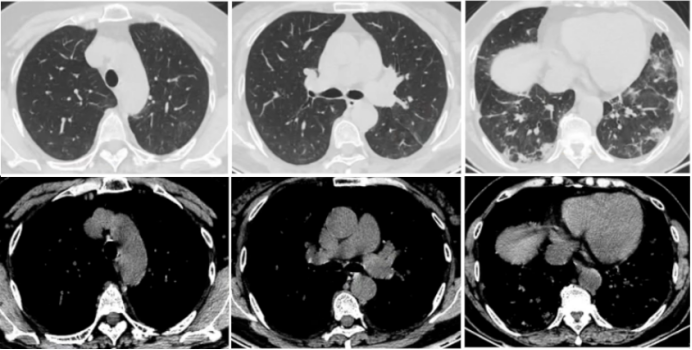

• 胸部CT: 双肺间质性炎症, 胸腔积液(图3)

图片

3  入院胸部CT(2023-11-06)